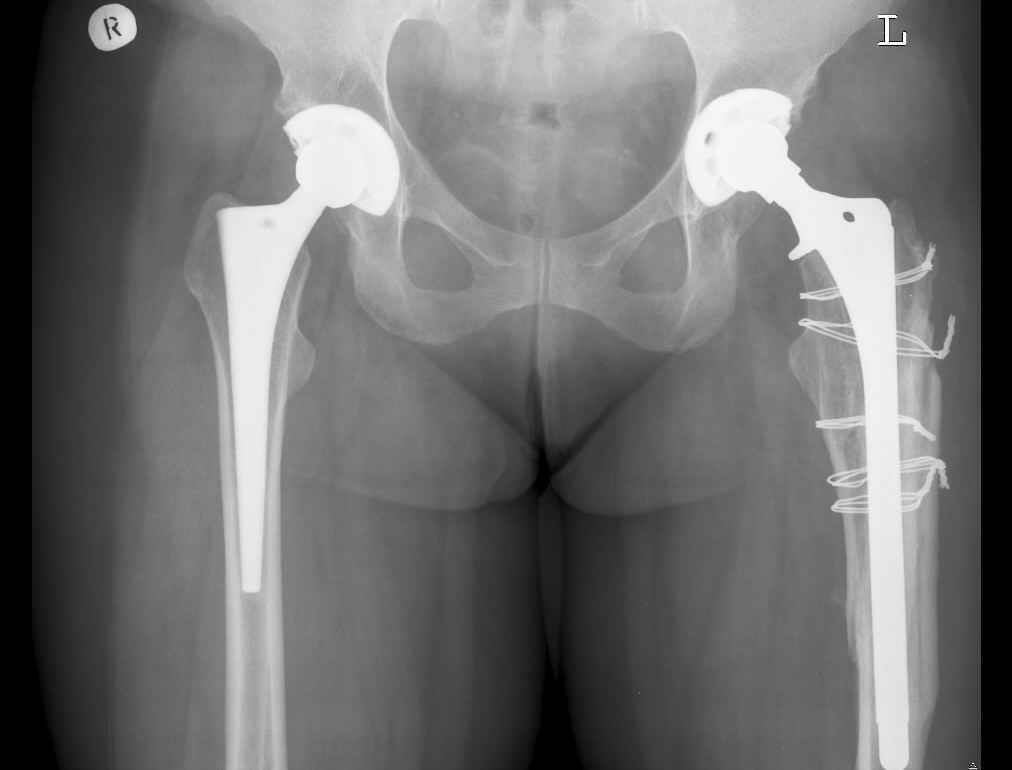

Анамнез: Болеет с 1995 года. В 2000 и 2001 годах произведено тотальное эндопротезирование обоих тазобедренных суставов (сначала левого затем правого). Сейчас в области левого бедра в в/3 имеется резкий отек, боль, крепитация. Диагноз:Состояние после тотального эндопротезирования обеих Т\Б суставов, перелом в/3 левого бедра. Нога уложена на шину Беллера с дисциплинирующим вытяжением. Тактика оперативного лечения? Заранее благодарю! С уважением, А.В.Владзимирский Донецкий НИИ травматологии и ортопедии

Привет Антон. Дальний Восток советует (правда ранее мы все учились в Украине - Харьков и Киев - мои школы ортопедии). Конкретика. Имеется

перипротезный перелом на фоне нестабильной ножки протеза. Для прогнозирования приличного результата у данного бедолаги я бы предложил -1.

Ревизию бедренного компонента 100%, замену ножки на длинную, скажем Вагнера или другую -модульную с дистальной фиксацией и обязательно! с костной

пластикой проксимального дефекта бедра чипсами или стружкой, но своими имеется дефект 2-3 типа по W. Paproski) + перелом. Ждать милости от времени

не стоит. 2. По поводу тазового компонента ситуация неопределенная (что стоит - не понял, стабильность не ясная, решение - при ревизии). Но замена при небходимости на б\ц + кросс линк полиэтилен или другую пару (по финансовой возможности клиента или клиники) может потребоваться.

В очередной раз вызывает удивление установка биполяра у молодого пациента, но дело не в этом. Имеется перелом с нестабильностью бедренного цементного компонента. Значительный дефект костной ткани проксимального отдела бедра.

Следует убрать ножку и остатки цемента, заменить на Вагнеровскую ножку (в крайнем случае на длинную цементную), добавить костную пластику проксимального отдела. Тазовый компонент заодно заменить на бесцементный.

Уважаемый Антон,

По Ванкуверовской классификации это 2А тип перипротезного перелома на фоне нестабильности ножки эндопротеза и остеолиза проксимального отдела бедра. Решение - удаление предыдущей ножки, имплантация ножки дистальной фиксации. Канал виден на ограниченном участке, исходя из увиденного, я бы предпочел цилиндрическую ножку 200 мм полнопокрытую. Фрагменты собрал бы вокруг ножки серкляжами. Если будут мелкие фрагменты, то есть смысл взять кортикальные аллографты и поджать фрагменты по типу вязанки хвороста. Отношение к чипсам двоякое - на любителя, главное - надежная дистальная фиксация ножки, обеспечивающая первичную стабильность. Что-то похожее мы оперировали несколько лет назад, качество первичных Р-грамм оставляет желать лучшего, но суть понятна. Результаты через 3 года.

Уважаемый коллега! Абсолютно согласна с мнением Рашида Муртузалиевича Тихилова: это перелом на фоне нестабильности, необходима длинная ножка с дистальной фиксацией, и без серкляжа не обойтись. Впадину тоже придется заменить.